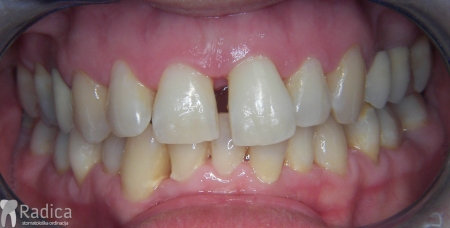

U sljedećem primjeru je fiksna ortodontska terapija rađena samo u donjoj čeljusti. Nakon toga pacijent je upućen svom stomatologu koji je napravio nove protetske radove u gornjoj i donjoj čeljusti.

Na sljedećoj slici mogu se vidjeti početak i kraj ortodontske terapije. Pacijentica je upućena od svog stomatologa nakon što nije bila zadovoljna izgledom osmjeha i odnosom zuba i gingive u privremenom protetskom radu. Napravljena je ortodontska terapija samo u gornjoj čeljusti a nakon toga novi privremeni protetski rad.